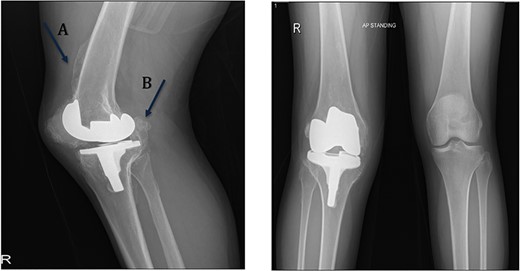

A 32-year-old female known case of rheumatoid arthritis affecting both knees presented to our clinic complaining of severe right knee stiffness post TKA 4-years-ago done in an outside facility (Figs. 1 and 2). She lives in a rural community and was on hydroxychloroquine, but her disease was active as she was not compliant to her medication. On physical examinations, the right knee was larger in size compared to the left knee without joint effusion. Range of motion was zero on flexion, −10° in extension. Standing knee X-ray showed HO around the prosthesis (Fig. 2). Computed tomography (CT) demonstrated extensive HO with implants fixed in place (Fig. 3). Revision surgery and replacement of the prostheses was considered to restore function.

Preoperative standing X-ray showing heterotopic ossification around the prosthesis with preserved knee joint. (A) Heterotopic bone extending proximally on the anterior surface of the femur. (B) Posterior heterotopic bone fusing the knee joint. Careful removal with osteotomes and bone curettes was necessary to remove the old implants.